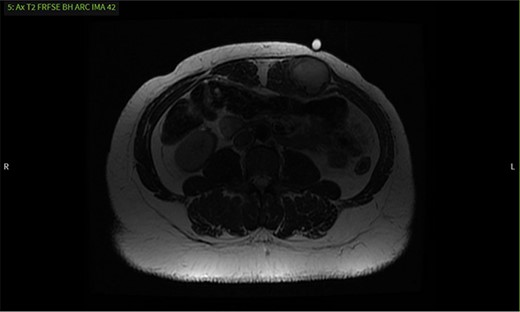

MRI shows a mass with well-defined margins and high signal intensity on T2 sequence.

It was difficult to delineate whether the mass was primarily cystic or solid based on the initial CT, so an ultrasound was ordered. The ultrasound revealed the mass had enlarged, now measuring 5.7 × 3.6 × 4.7 cm. Internal vascularity was present, making the diagnosis of a solid mass more likely than a seroma (Fig. 2). An MRI redemonstrated the mass embedded in the left rectus muscle (Fig. 3). It had well-defined margins with high signal intensity on T2 sequence and low signal intensity on T1. On post-contrast sequences, the mass had homogeneous enhancements and a thick enhancing wall, most compatible with an intramuscular myxoma. However, without tissue biopsy, other solid tumors could not be dismissed, such as desmoid.

This is consistent with the current literature on the use of MRI as an imaging modality for desmoid tumors [1, 3]. Their presentation on MRI varies, as these tumors are thought to have early, intermediate and later stages that differ in composition [1]. In the early stage, the composition is more myxoid, with low intensity on T1 sequence and high intensity on T2, consistent with our MRI findings. At the intermediate stage, fibrous elements begin to replace the myxoid elements leading to a mixed intensity T2. Finally, in the later stage, the myxoid background is completely replaced with fibrous elements leading to low intensity on both T1 and T2. Our patient likely presented in an earlier stage and therefore had features most similar to that of a benign myxoma as opposed to a later stage desmoid tumor.